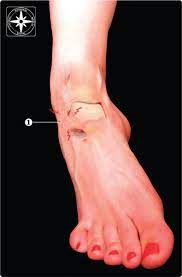

Injury to this ligament results in swelling and pain on the outside of the ankle. Complete tear of the ligament significant tenderness and swelling around the ankle if the doctor pulls or pushes on the ankle joint in certain movements, substantial instability occurs in a grade 2 sprain, some but not all of the ligament fibers are torn. The anterior talofibular ligament (atfl) connects the talus to the fibula and is. Mild instability occurs due to partial tears of the lateral ligaments. Many ankle ligament injuries occur when the foot is twisted inwards. If the force is more severe, the calcaneofibular ligament is also damaged. Sprains with complete ligament corrected tears (grade iii) may require surgical intervention. In regards to a grade i injury, the anterior talofibular ligament (atfl) is involved.

The anterior talofibular ligament (atfl) connects the talus to the fibula and is. Depends from the grade of the torn ligament. Injuries typically occur during plantar flexion and inversion; A grade 2 ankle sprain describes a partial ligament tear, and grade 3 sprains involve complete tearing of one or more ankle ligaments. The most common and significant ligament tears include tears in the anterior talofibular ligament (atfl), calcaneofibular ligament (cfl), and the large deltoid ligament complex. Anterior talofibular ligament injury is the most common of the ligament injuries that can occur as part of the lateral ligament complex injuries 2. Complete tear of the ligament significant tenderness and swelling around the ankle if the doctor pulls or pushes on the ankle joint in certain movements, substantial instability occurs in a grade 2 sprain, some but not all of the ligament fibers are torn. Involves moderate pain and swelling and difficulty walking. Large tear of the atfl. The anterior tibiofibular (atfl), calcaneofibular (cfl) and posterior talofibular (ptfl) ligaments. Ankle sprains (stretching of the lateral ankle ligaments) are one of the most common injuries to occur in the lower extremity. Symptoms include a broader region of point tenderness over the lateral aspect of the ankle, a painful gait or inability to ambulate, bruising and localized swelling due to tearing of the anterior joint capsule, atfl, and surrounding soft tissue structures. This is the ligament that is most commonly sprained with lateral ankle sprains.

Symptoms include a broader region of point tenderness over the lateral aspect of the ankle, a painful gait or inability to ambulate, bruising and localized swelling due to tearing of the anterior joint capsule, atfl, and surrounding soft tissue structures.